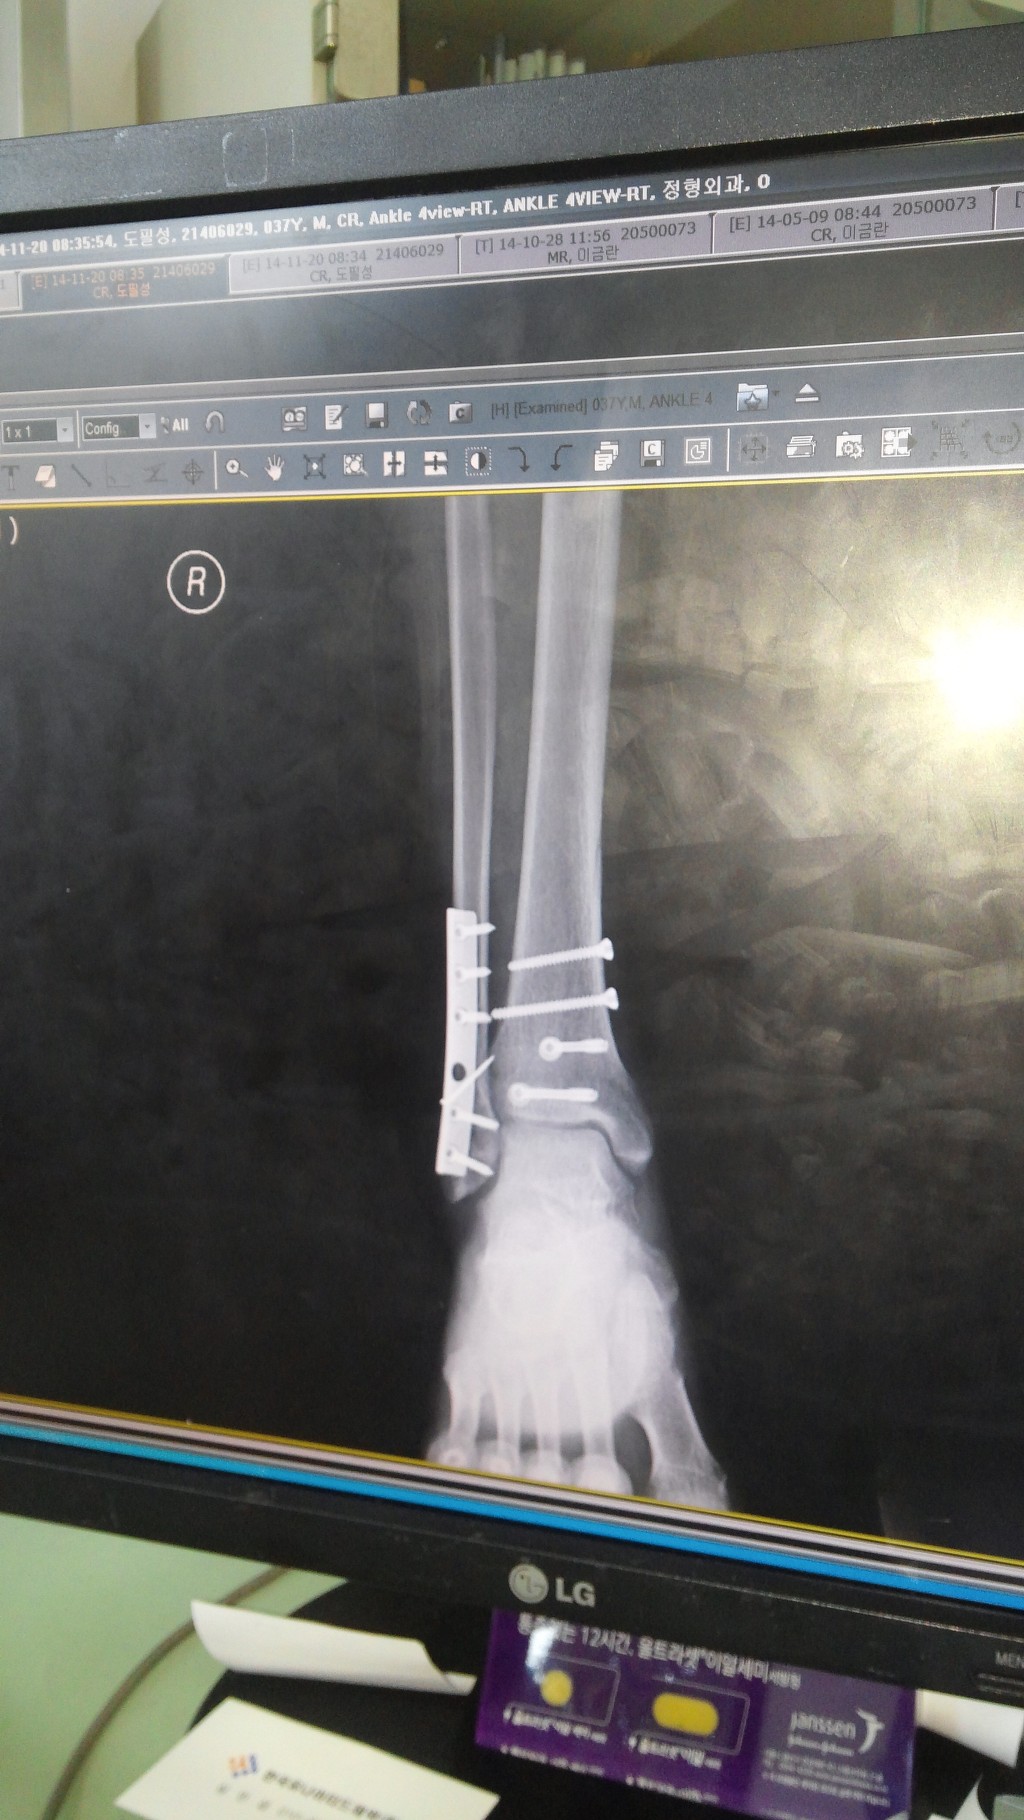

우측 족관절 원위 경골 관절내 골절, 외측과 골절, 후과 골절 수술 및 재활 과정 적습니다.15주차입니다.

다행히 붓기가 빠져서 13일 수술하였습니다. 4시간 수술하였고요. 하반신 마취하였습니다. 무통 달아놔서 그런지 큰 통증은 없었습니다.수술후 마취가 안 풀려 오줌은 마려운데 나오지가 않으니 통증이 장난 아니더군요. 휴~

8월 13일 수술

11월 25일 수술한 병원 진료. 사진 찍고 잘 붙었다며 이제 핀 제거 할때 오라고 하시네요. 수술후 1년에서 1년 6개월 후에 빼라고 합니다. 검색해보니 제거하니 엄청 부드럽고 편하다고 하네요. 저두 최대한 빨리 빼고 싶네요. 얼른 내년 여름이 와서 제거하고 싶네요.